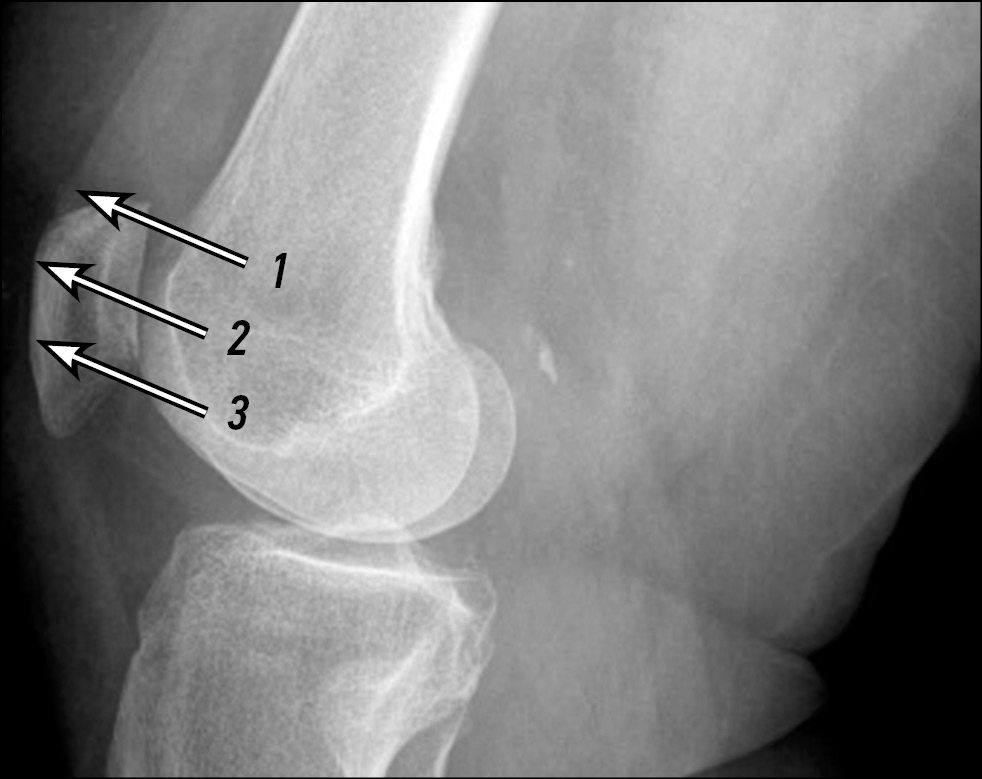

Правильность размещения ультразвукового датчика корректировали для достижения визуализации плоскостных сонографических ориентиров с помощью рентгенографического снимка (рис. 4). Эти положения ультразвукового трансдьюсера позволяли визуализировать медиальную границу надколенника, надколенниковый хрящ и выпуклую границу медиального мыщелка бедренной кости, а также МПСС. После определения правильного расположения первым пальцем левой руки смещали надколенник в медиальную сторону сустава во время динамической сонографии (см. рис. 1). Правильное расположение трансдьюсера определялось с помощью трех плоскостных сонографических ориентиров: выпуклая, округлая передняя поверхность медиальной части бедренной кости; медиальная граница надколенника, покрытая гипоэхогенным эхом хряща; МПСС.

Рис. 4. Рентгенограмма коленного сустава. Позиции ультразвукового датчика при проведении исследования: 1 — датчик расположен неправильно, более проксимально; 2 — датчик расположен в правильной позиции; 3 — датчик расположен неправильно, более дистально

Fig. 4. X-ray of the knee joint. Positions of the ultrasonic transducer during the study: 1 — the transducer is located incorrectly, more proximally; 2 — the sensor is in the correct position; 3 — the sensor is located incorrectly, more distally